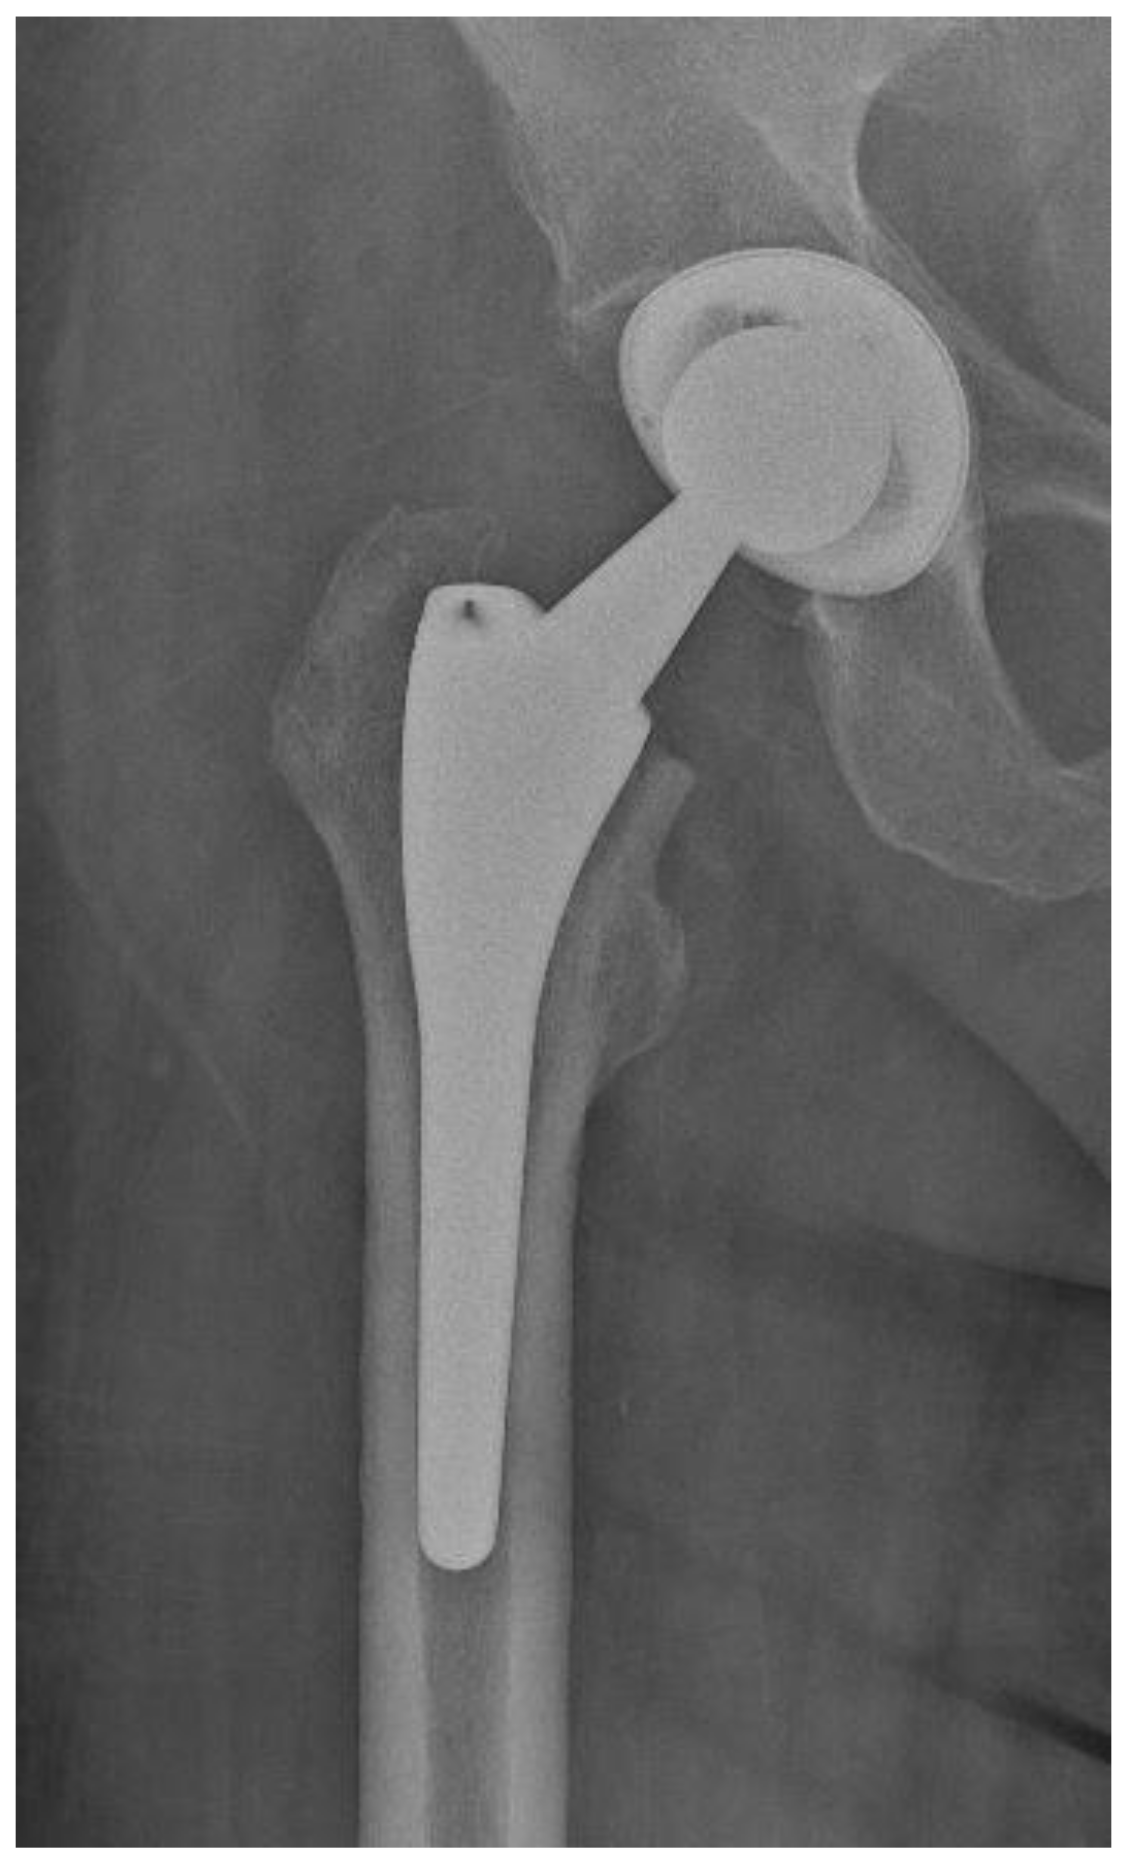

Of the 84 patients enrolled in this study, 44 patients (52.4%) received a THA with a straight stem (group A) (Figure 1 and Figure 2) and 40 patients (47.6%) received a THA with an anatomical stem (group B) (Figure 3 and Figure 4).

Figure 3.

Antero-posterior X-rays view of a total hip arthroplasty with anatomical stem (group B).